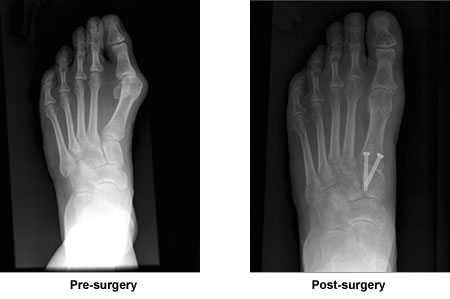

One of my friends has had two additional surgeries to re-do her bunion repair, all done here in N.H. in the last three years. I kept telling her to drive to Boston and see Dr. Leavitt when she needed the first re-do. Sadly her foot is a mess. Mine is great three years later and I had more work done than she did. And she's younger than me too. So thank you, Dr. Leavitt, for my bunion surgery, and that I only had to have it done once!